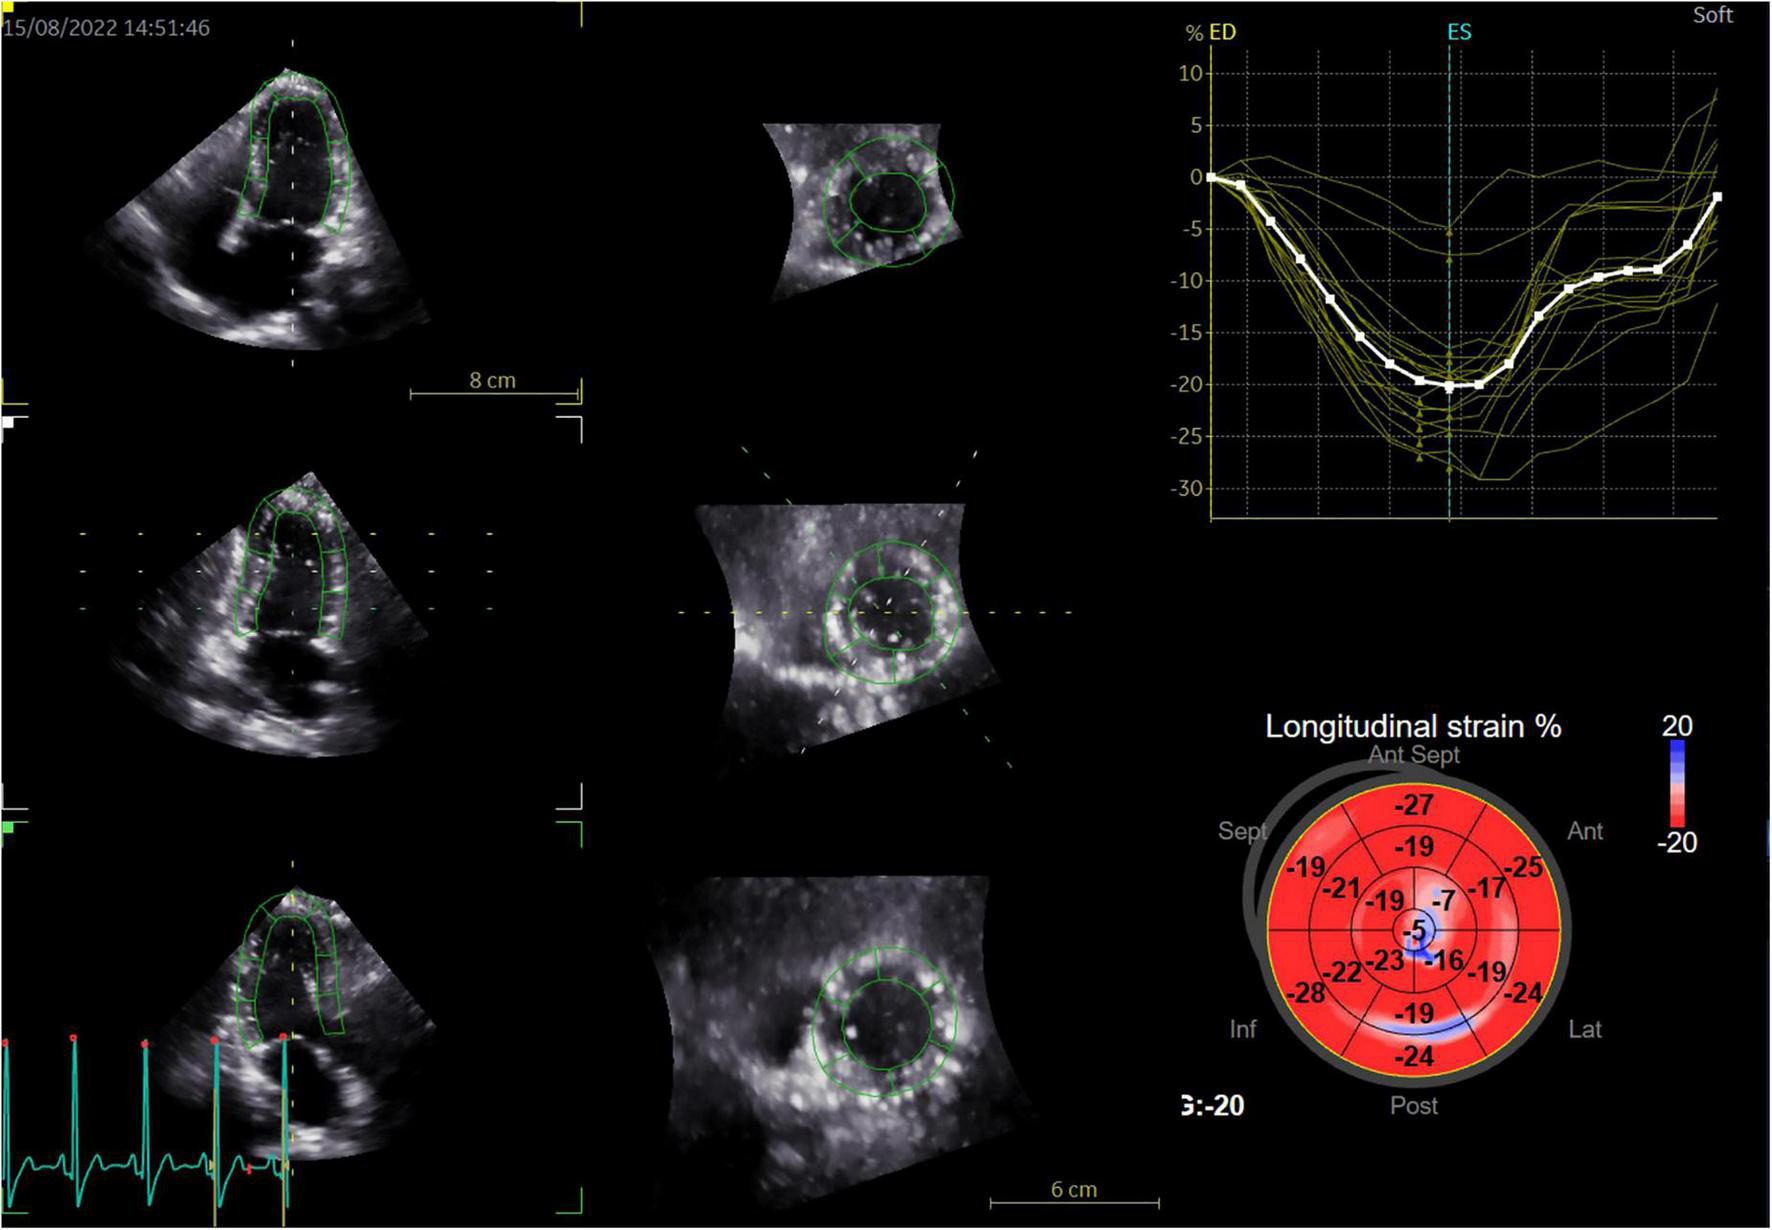

Three dimensional strain analysis is mainly used to measure myocardial deformation in three-dimensional space. After importing the 3D gray-scale images into the workstation, the system will automatically track the endocardial surface, and the region of interest can be manually adjusted if necessary. The system automatically generates a color-coded 17 segmental illustration of the bull eye and strain parameter curve of each segment (Figure 1). The weighted mean of the regional values from the 17 myocardial segments was also calculated to obtain parameters, including GLS, GCS, GRS, and GAS.

FIGURE 1

Representative diagram of three-dimensional speckle-tracking strain measurements in a patient with breast cancer treated with chemotherapy (left panel: sections generated by 3D full-volume image cut of the LV, right panel: the color-coded bull’s eye plot of the longitudinal strain in the LV 17 segment and corresponding longitudinal strain regional values).